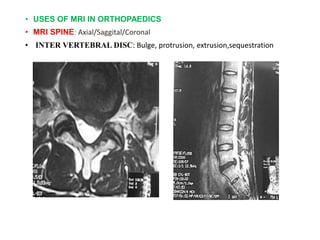

• USES OF MRI IN ORTHOPAEDICS

• MRI SPINE: Axial/Saggital/Coronal

• INTER VERTEBRAL DISC: Bulge, protrusion, extrusion,sequestration